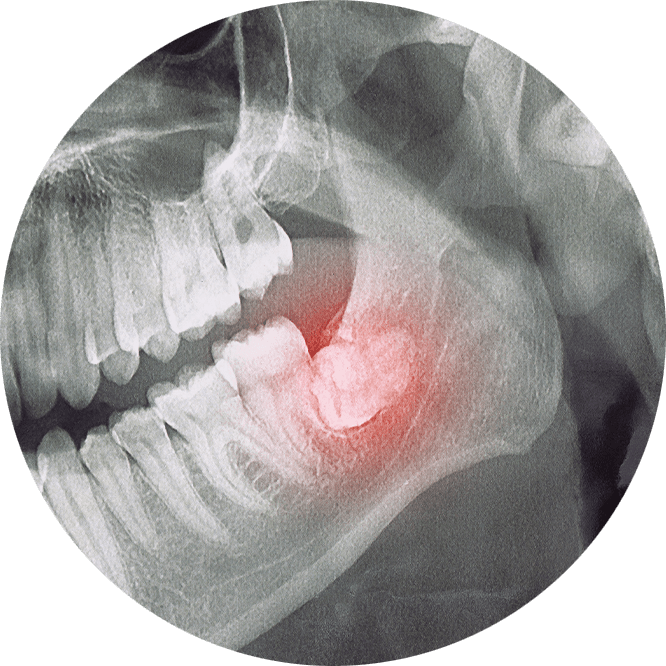

Due to the position at the back of the mouth, lack of space or an obstruction, wisdom teeth (third molars) frequently become partially or completely impacted. Impacted wisdom teeth are hard to clean so they’re prone to bacteria buildup. This can lead to decay, pain, swelling, gum disease and cysts that can harm adjacent teeth and bone. Dr. Kari Mann offers wisdom tooth removal in Cape Coral, FL under local anesthesia and sedation, however, more complex cases may be referred to an oral and maxillofacial surgeon.